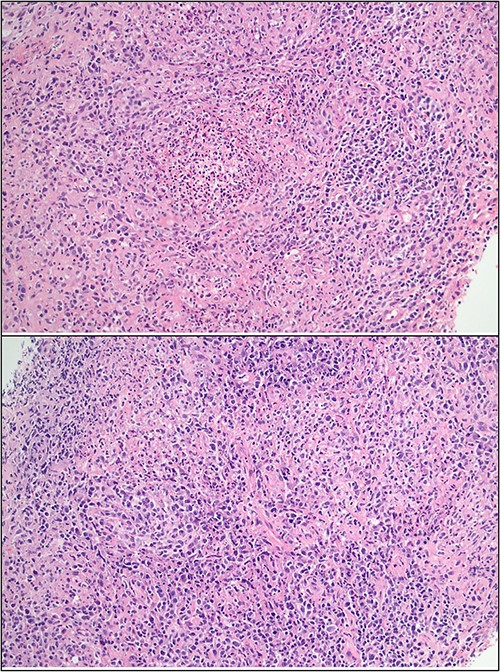

Additional PCR testing for B. henselae and Toxoplasma gondii was conducted on the core biopsy specimen, and B. henselae DNA was detected. To investigate the possibility of comorbid PTLD, excisional node biopsy was performed. Histology demonstrated histiocytic granulomas with a surrounding lymphoid infiltrate; crucially, there was no effacement of nodal architecture on the full specimen (Fig. 4). At this stage, serum B. henselae IgG was repeated and returned a positive result (>1: 1024; cut-off 1: 256), indicating seroconversion within the 15-day period from his negative B. henselae IgG at admission.

Excisional biopsy histology (A) foci of necrotising granulomatous inflammation; (B) presence of EBER-ish-positive cells.

While we remained wary of concomitant PTLD, there were two reassuring factors in this patient’s case. First, PTLD-associated lymphocytes characteristically degrade the underlying tissue [4]; therefore, the finding of wholly preserved nodal architecture on excisional biopsy considerably reduces suspicion for polymorphic PTLD. Second, the patient’s EBV load was negative on discharge despite uninterrupted immunosuppressive therapy.

The gold standard for delineating CSD from PTLD is a histological examination of an excisional biopsy, allowing evaluation of the nodal architecture. Malignant PTLD infiltrate almost invariably results in nodal effacement; in contrast, preserved nodal architecture is suggestive of CSD or early stage hyperplasia [6]. Though not evidenced in this case, necrotising granulomas offer a further histologic clue: as an indicator of impaired pathogen clearance, they are a common feature in CSD [7] but absent in PTLD.